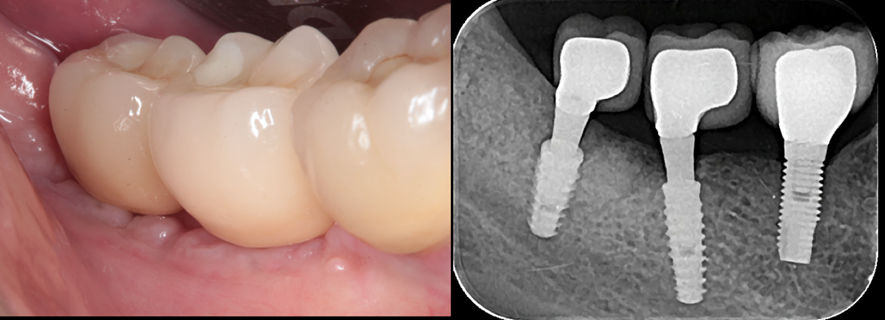

Figura 3 – Imagens clínica e radiográfica no momento da colocação das coroas sobre os implantes 46 e 47 – Cone Morse Maestro (Implacil Osstem – São Paulo – Brasil). Observar a normalidade do tecido ósseo peri-implantar.